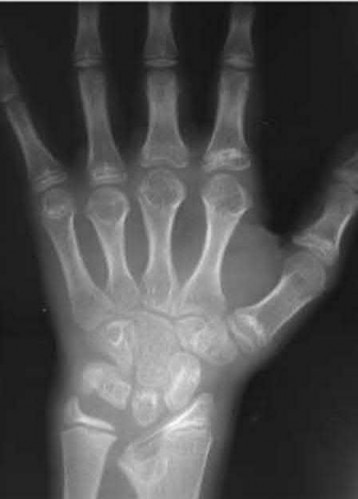

A 51-year-old female presents with an acute inability to extend her thumb, four months after she was treated with cast immobilization for a minimally-displaced distal radius fracture. What is the most appropriate treatment at this time?

A rare complication of non-displaced or minimally displaced fractures of the distal radius treated with a cast is a delayed rupture of the extensor pollicis longus (EPL) tendon. The EPL is the primary extensor of the interphalangeal joint of the thumb and also assists with metacarpophalangeal extension.

Extensor indicis proprius transfer to the EPL is the most widely used and reported treatment for this condition.

Magnussen et al. reviewed results of EIP transfer following ruptures of the EPL, with 19/21 good results. None of the cases had any loss of independent index finger extension although index extensor strength reduced to half of that of the contralateral side.

Hove et al. reported a similar satisfaction rate following treatment of 15 patients. In his series of 4,400 distal radius fractures treated over a 5 year period, the incidence of delayed tendon rupture following distal radius fracture was 0.3 percent.